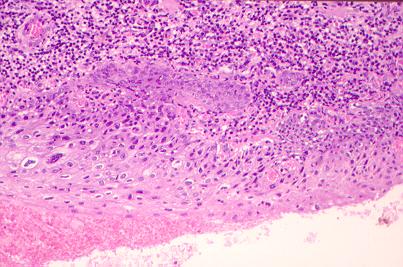

Fig. 1.- Zona de carcinoma in situ de células escamosas con cambios koilociticos. (H-E.).